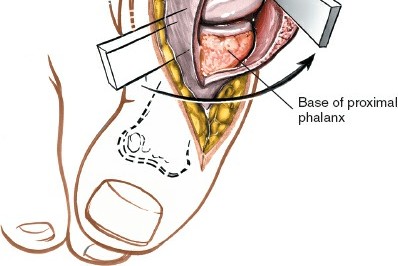

Safe Zones for Lateral Capsular Release

When a lateral capsular release is indicated to correct residual deformity, it must be executed with precision. The safe zone for a lateral capsular release spares all perforators entering the metatarsal head proximally and all perforators entering the proximal phalanx distally. This is achieved as long as the capsulotomy is performed strictly in line with the metatarsophalangeal (MTP) joint in the coronal plane.

Figure A demonstrates a severe iatrogenic hallux varus following a McBride bunionectomy, characterized by medial deviation of the proximal phalanx and subluxation of the tibial sesamoid.